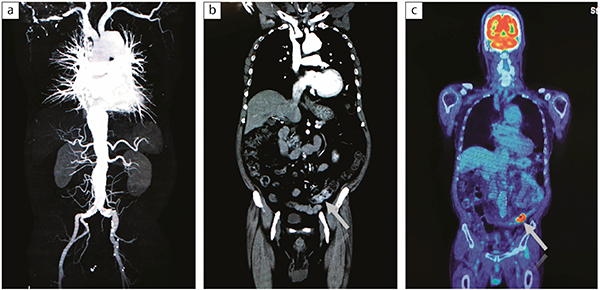

図1 想定外の病変が見つかった症例

大動脈瘤精査の症例でCTアンギオグラフィが撮影された(a)。冠状断で下行結腸に濃染があり,結腸がんが疑われた(b)。後日行われたFDG-PET/CTで腫瘍に集積があった(c)。